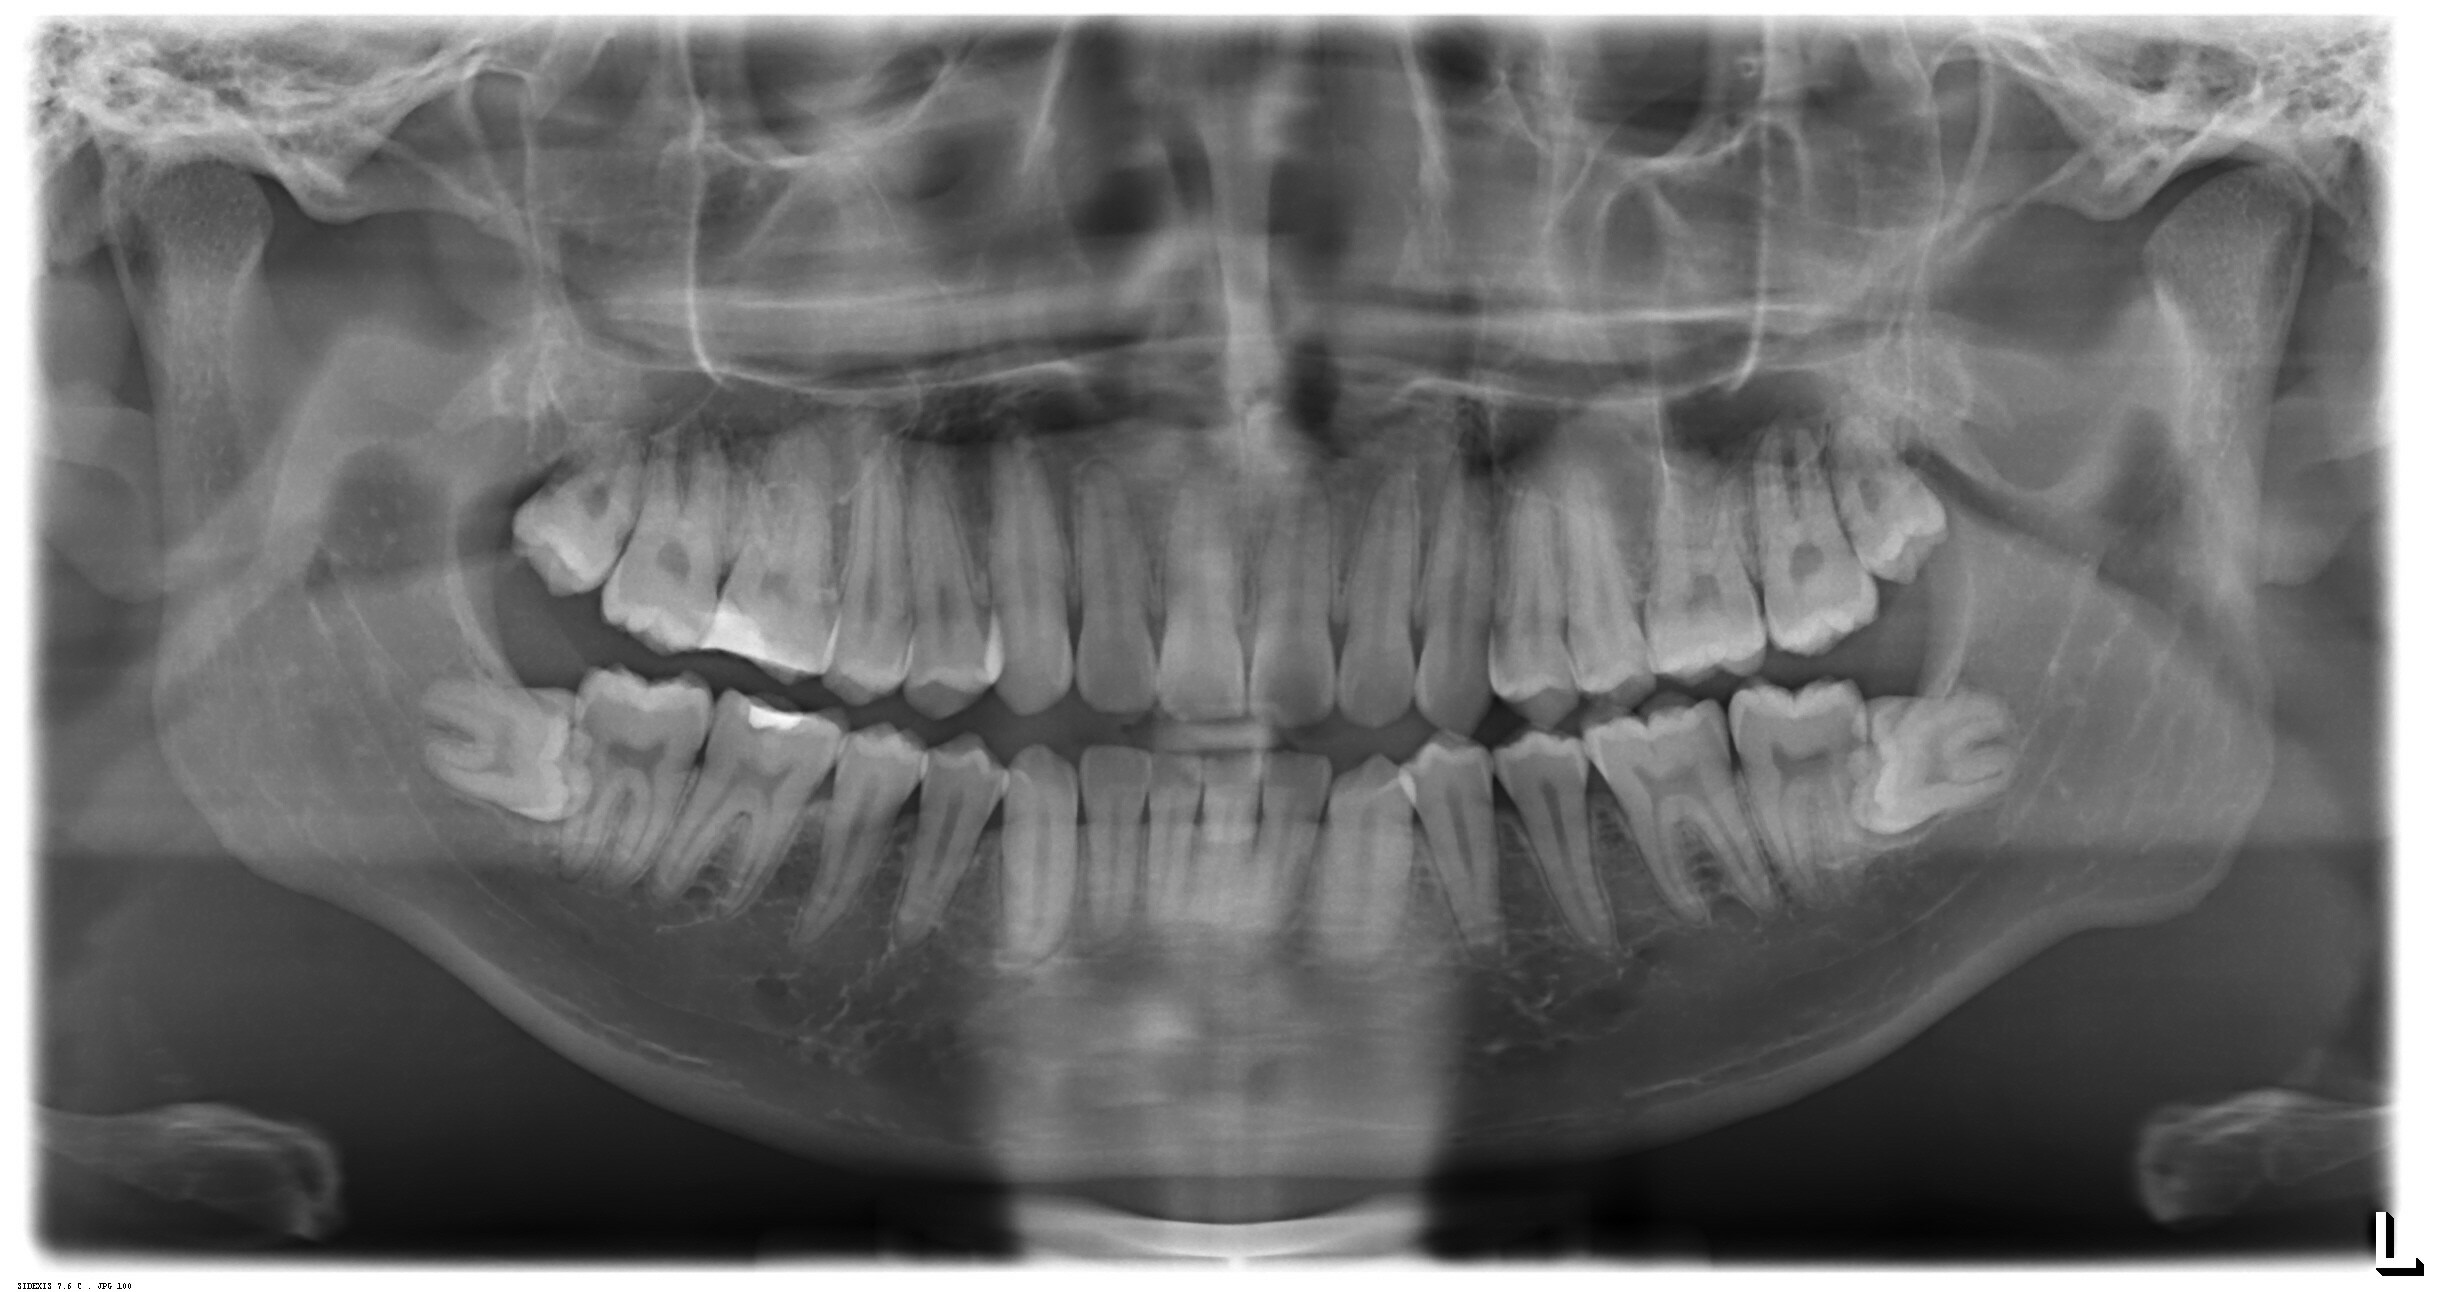

I think this is pretty common. Mine were almost the same as this.

Mine look identical to this too, they haven't moved in over 20 years and don't cause me any discomfort.

I xrayed them out 3 years ago and they just begin to murder me since Sunday.

Both my bottom ones are impacted like that but only one broke skin. I’m afraid to get it removed though because the doctor can’t see if it goes that deep, he said I may experience loss of feeling.

I was around your age when i first being aware of them 4-5 years ago. They just began to murder me since sunday. Extreme migraine and can't sleep at all, feel like the molar is about to explode to dust due to the pressure. I count day by day ti the weekend so i can take it out.